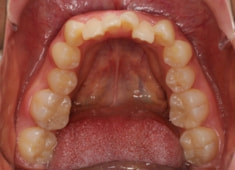

治療前

治療開始時